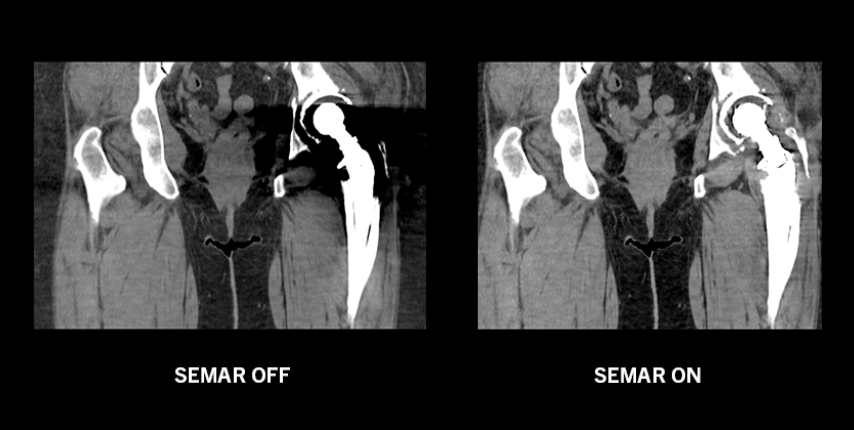

Технология SEMAR

Алгоритм даёт возможность практически полностью устранить металлические артефакты, улучшая визуализацию имплантов, опорной кости и прилегающих мягких тканей для более четкой и уверенной диагностики.